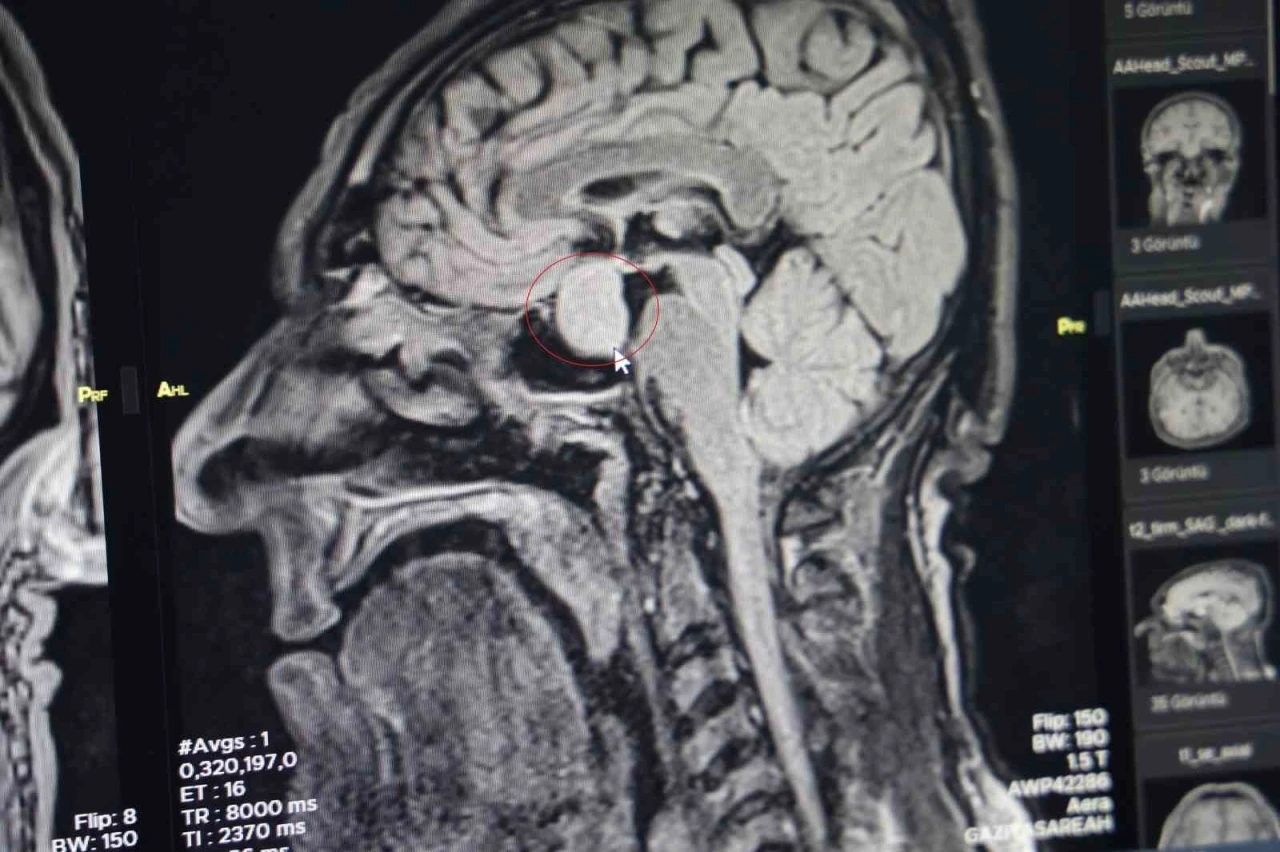

Hastanın dış merkezlerde çekilen MR’larında hipofiz bölgesinde bir iyi huylu tümör tespit edilmesi ve tavsiye üzerine kliniğine başvurduğunu belirten Dr. Çetin, hastanın yatışını yapıp ileri tetkiklerini yaptıklarını kaydetti.

Dr. Çetin, hormonlarına baktıklarında hastanın büyüme hormonları yüksek olduğunu söyleyerek, "Hastayı yapacağımız ameliyat ile ilgili bilgilendirdik. Hastanemizde ilk defa burundan kapalı yöntemle girilerek hipofiz tümörüne müdahale ettik. Allah’a şükür sağ salim bir şekilde, her hangi bir komplikasyon gelişmeden tümörü aldık. İki gün sonra da hastamızı taburcu ettik. Operasyonumuz 2-2,5 saat sürdü. Herhangi bir riskle karşılaşmadık. Hastamızın genel durumu şu an gayet iyi. Kan tetkiklerinde ve hormon düzeyinin de düştüğünü büyük bir memnuniyetle gözlemledik" dedi.

"Kendi açımız ve hastanemiz açısından güzel oldu, gururlandık" diyen Dr. Çetin, "Hipofiz bezinde yetmezlik ve görme sinirlerinde baskı yaptığı zaman görme kaybına neden olabilmektedir. Bu hastamızda ameliyat öncesi görme kaybı bir miktar vardı. Büyüme hormonu oldukça yüksekti. Tümörü boşalttığımız için hormon düzeyi yarıya düştü. 2-3 hafta sonra kontrole gelecek bir daha ölçme imkanı bulacağız. Bu hastalar genelde şimdiye kadar büyükşehirlere gitmekteydiler. Bundan sonra bu tür ameliyatları gerçekleştirme imkanı bulacağız" şeklinde konuştu.